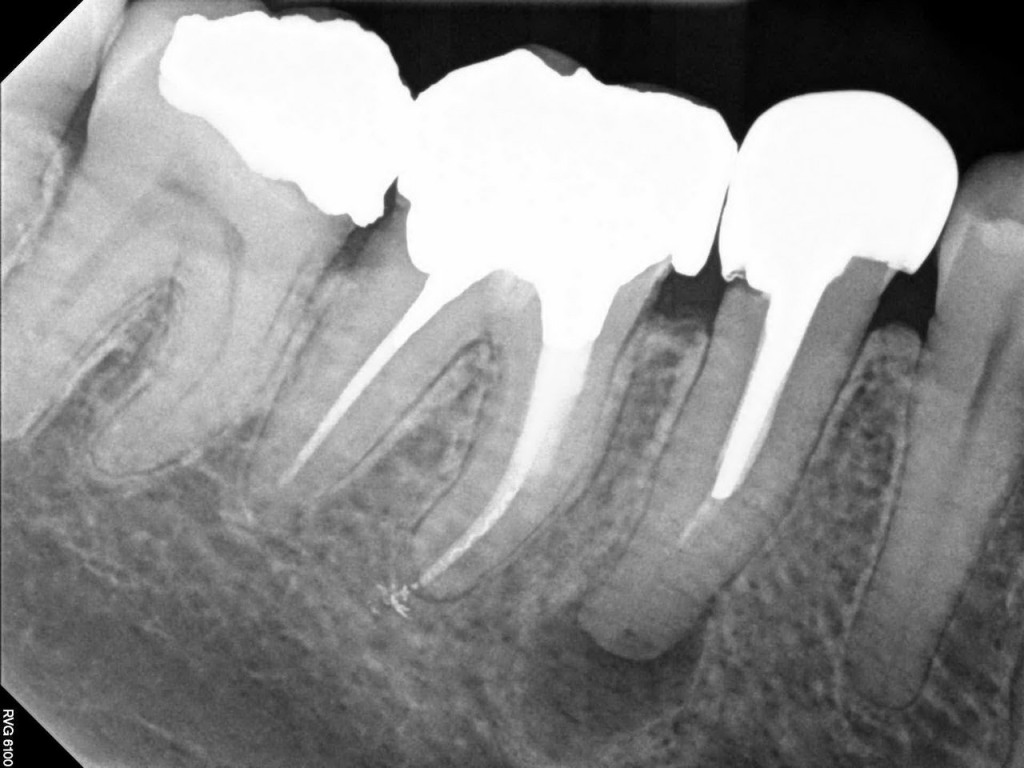

Diş röntgeni diş, çene kemikleri ve diş eti seviyesinin klinik muayenede görülmeyen kısımları hakkında fikir edinmek amacıyla X ışını yardımıyla elde edilen radyolojik görüntülerin adıdır. Diş röntgenleri tedaviye başlanmadan önce teşhis, tanı ve planlama amaçlı istenebileceği gibi, tedavi süresince ve tedavi sonrasında kontrol amaçlı olarak da istenebilmektedir.